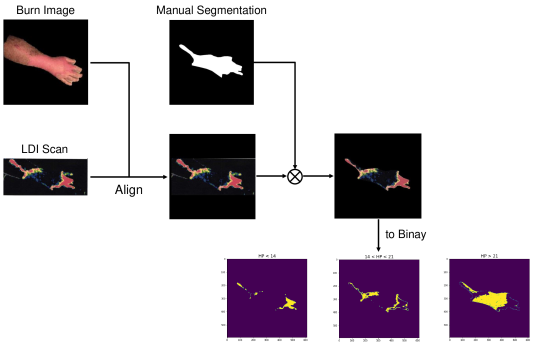

In order for the LDI scans to be comparable with BAM binary segmentations, a number of processing steps were conducted. LDI scans can have different sizes, scales, and cropping in comparison to their corresponding burn images. As BAM uses the burn 2D colour images as the input for creating the binary burn segmentations, the LDI scans were first aligned with their corresponding burn images and converted into the same size as those images. Once the LDI scans are aligned with input images and their colors are processed in order to create binary masks, quantitative comparisons with BAM segmentations were conducted. For this purpose, we utilised the manual segmentations of burn areas from burn images validated by clinicians.

Moreover, as discussed later, it was discovered that the LDI scan color palette, which demonstrates different healing potentials, would classify uninjured areas and background noise in the image as burns with poor blood flow. In a clinical setting, this misclassification does not lead to a serious issue as scans are reviewed by clinicians who can easily differentiate between normal skin/background and burn area. However, since the processing of LDI scans is conducted by computer vision, this issue needed to be resolved. This was addressed by removing the non-burn areas from the LDI scans before processing LDI scans by multiplying the aligned LDI scans with the manual segmentations of burn areas resulting in LDI scans that show various healing potentials (or various degrees of burn) in the burn area only.